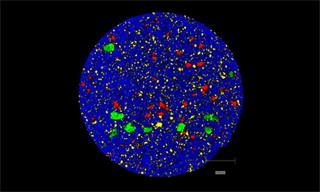

Rapidly generate images of your formulations with StreamLine™. This uses line focus illumination, allowing you to use higher laser powers without risk of sample damage, thereby reducing experiment times.

With the RA802 pharmaceutical analyser you can achieve imaging speeds of over 1500 spectra/s. It takes less than 2 minutes, from placing a standard tablet in the system, to generate a full, high resolution Raman image.

Generate images of formulations

Ensure your chemical images are representative; use Renishaw's StreamLine. You can change resolution to suit your domain size and, because Renishaw's WiRE software can cope with massive data files, you can analyse over the entire sample surface. Powerful Renishaw features, such as Slalom (to ensure the whole surface is sampled) and HD imaging (to get crisp clear images), provide all the options you need, whatever your formulation.